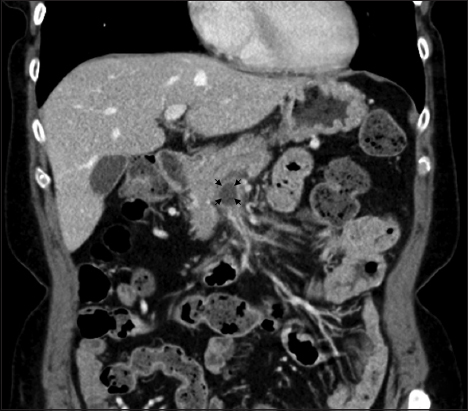

A 65-year-old female presented for evaluation of upper abdominal pain. Her clinical examination was normal. Serum amylase and lipase were normal. Contrast-enhanced computed tomography (CECT) of the abdomen showed a 35 mm cystic lesion around the mid body of the pancreas (Fig. 1) and she was referred to our center as “pancreatic cyst” requiring resection.

Figure 1 Contrast-enhanced computed tomography of the abdomen showing cystic lesion in the head of the pancreas

A careful evaluation of the CECT showed that the lesion was in fact extra-pancreatic; a hypodense thrombus within an aneurysmal dilatation of the superior mesenteric vein (SMV) measuring 35 mm and mimicking a “pancreatic cyst”. She was negative for protein C deficiency, protein S deficiency, antithrombin III deficiency, factor V Leiden mutation, prothrombin G20210A, hyperhomocysteinemia and antiphospholipid antibodies. Antinuclear antibody and anti cytoplasmic nuclear antibody were negative. Treatment with warfarin for 3 months after a prior low molecular weight heparin bridging showed gradual resolution of thrombus with decrease in the size of the aneurysm (Fig. 2, coronal view). Thus a surgery was averted.

Figure 2 Contrast-enhanced computed tomography of the abdomen one month later showing partial resolution of thrombus in the superior mesenteric vein with decrease in size